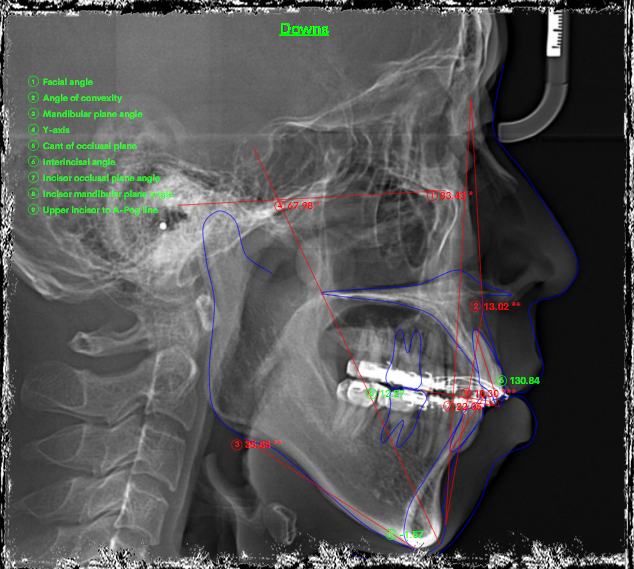

Điều trị những trường hợp bật chân răng do niềng hỏng là rất khó khăn và phức tạp. Trường hợp này là một bệnh nhân được niềng răng ở nước ngoài, sau đó hết thời gian lao động mà bệnh nhân chưa hoàn thành điều trị và được chuyển về việt nam để điều trị tiếp. Tuy nhiên, khi BN đến với phòng khám làm gặp tình trạng mất torque rất nặng ở hàm dưới đến mức trên CBCT không còn cả bản xương ngoài- trong. Nên nhóm răng cửa hàm dưới không thể can thiệp gì hơn.

Kế hoạch: chỉnh torque, đóng nốt khoảng và chỉnh khớp cắn 2 hàm, hoàn thiện và kết thúc trong 1 năm